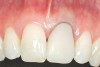

The 2-month postoperative view can be seen in Figure 13 through 15. Note the color match of the tissue, balance of the facial heights of contour, and zones of attached keratinized tissue present.

Figure 13  Case One The 2-month postoperative view, maxillary right.

Figure 13